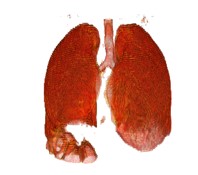

2.5 效果

以下图片是使用3dslicer渲染出来的。